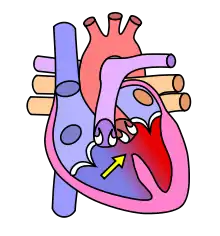

Cardiovascular System

The cardiovascular system, in addition to needing to maintain itself within certain levels, plays a role in maintenance of other body systems by transporting hormones (heart secretes Atrial Natriuretic Peptide and Brain Natriuretic Peptide, or ANP and BNP, respectively) and nutrients (oxygen, EPO to bones,etc.), taking away waste products, and providing all living body cells with a fresh supply of oxygen and removing carbon dioxide. Homeostasis is disturbed if the cardiovascular or lymphatic systems are not functioning correctly. Our skin, bones, muscles, lungs, digestive tract, and nervous, endocrine, lymphatic, urinary and reproductive systems use the cardiovascular system as its "road" or "highway" as far as distribution of things such as nutrients, oxygen, waste products, hormones, drugs, etc. There are many risk factors for an unhealthy cardiovascular system. Some diseases associated are typically labeled "uncontrollable" or "controllable." The main uncontrollable risk factors are age, gender, and a family history of heart disease, especially at an early age.

The cardiovascular system also contains sensors to monitor blood pressure, called baroreceptors, that work by detecting how stretched a blood vessel is. This information is relayed to the Medulla Oblongata in the brain where action is taken to raise or lower blood pressure via the autonomic nervous system.